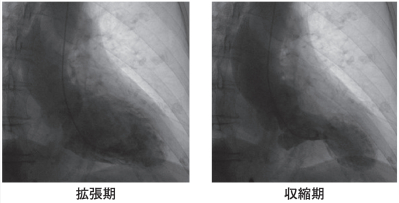

血液生化学所見:AST 29 U/L、ALT 99 U/L、CK 184 U/L(基準 30~140)、 脳性ナトリウム利尿ペプチド〈BNP〉952 pg/mL(基準 18.4 以下)。来院時の心電図を別に示す。心エコー検査で左室心尖部を中心とする無収縮領域と、左室基部の過収縮を認めた。緊急冠動脈造影検査を行ったが、冠動脈主幹部に有意な狭窄や閉塞を認めなかった。引き続き行った左室造影写真を別に示す。